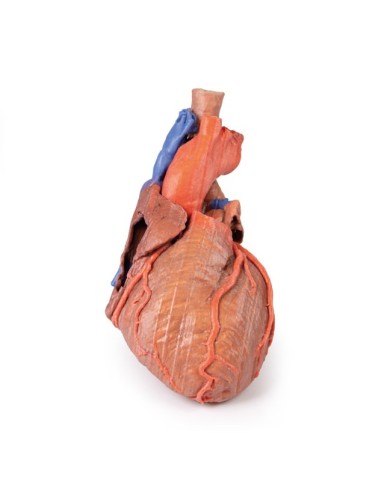

Modello di cuore di alta qualità scomponibile in 5 parti

Modello di cuore di alta qualità scomponibile in 5 parti

La parete anteriore del cuore è staccabile per poter vedere i ventricoli.

Realizzato in stampa 3D ad elevatissima risoluzione a colori.

Realizzato in stampa 3D ad elevatissima risoluzione a colori.

Realizzato in stampa 3D ad elevatissima risoluzione a colori.